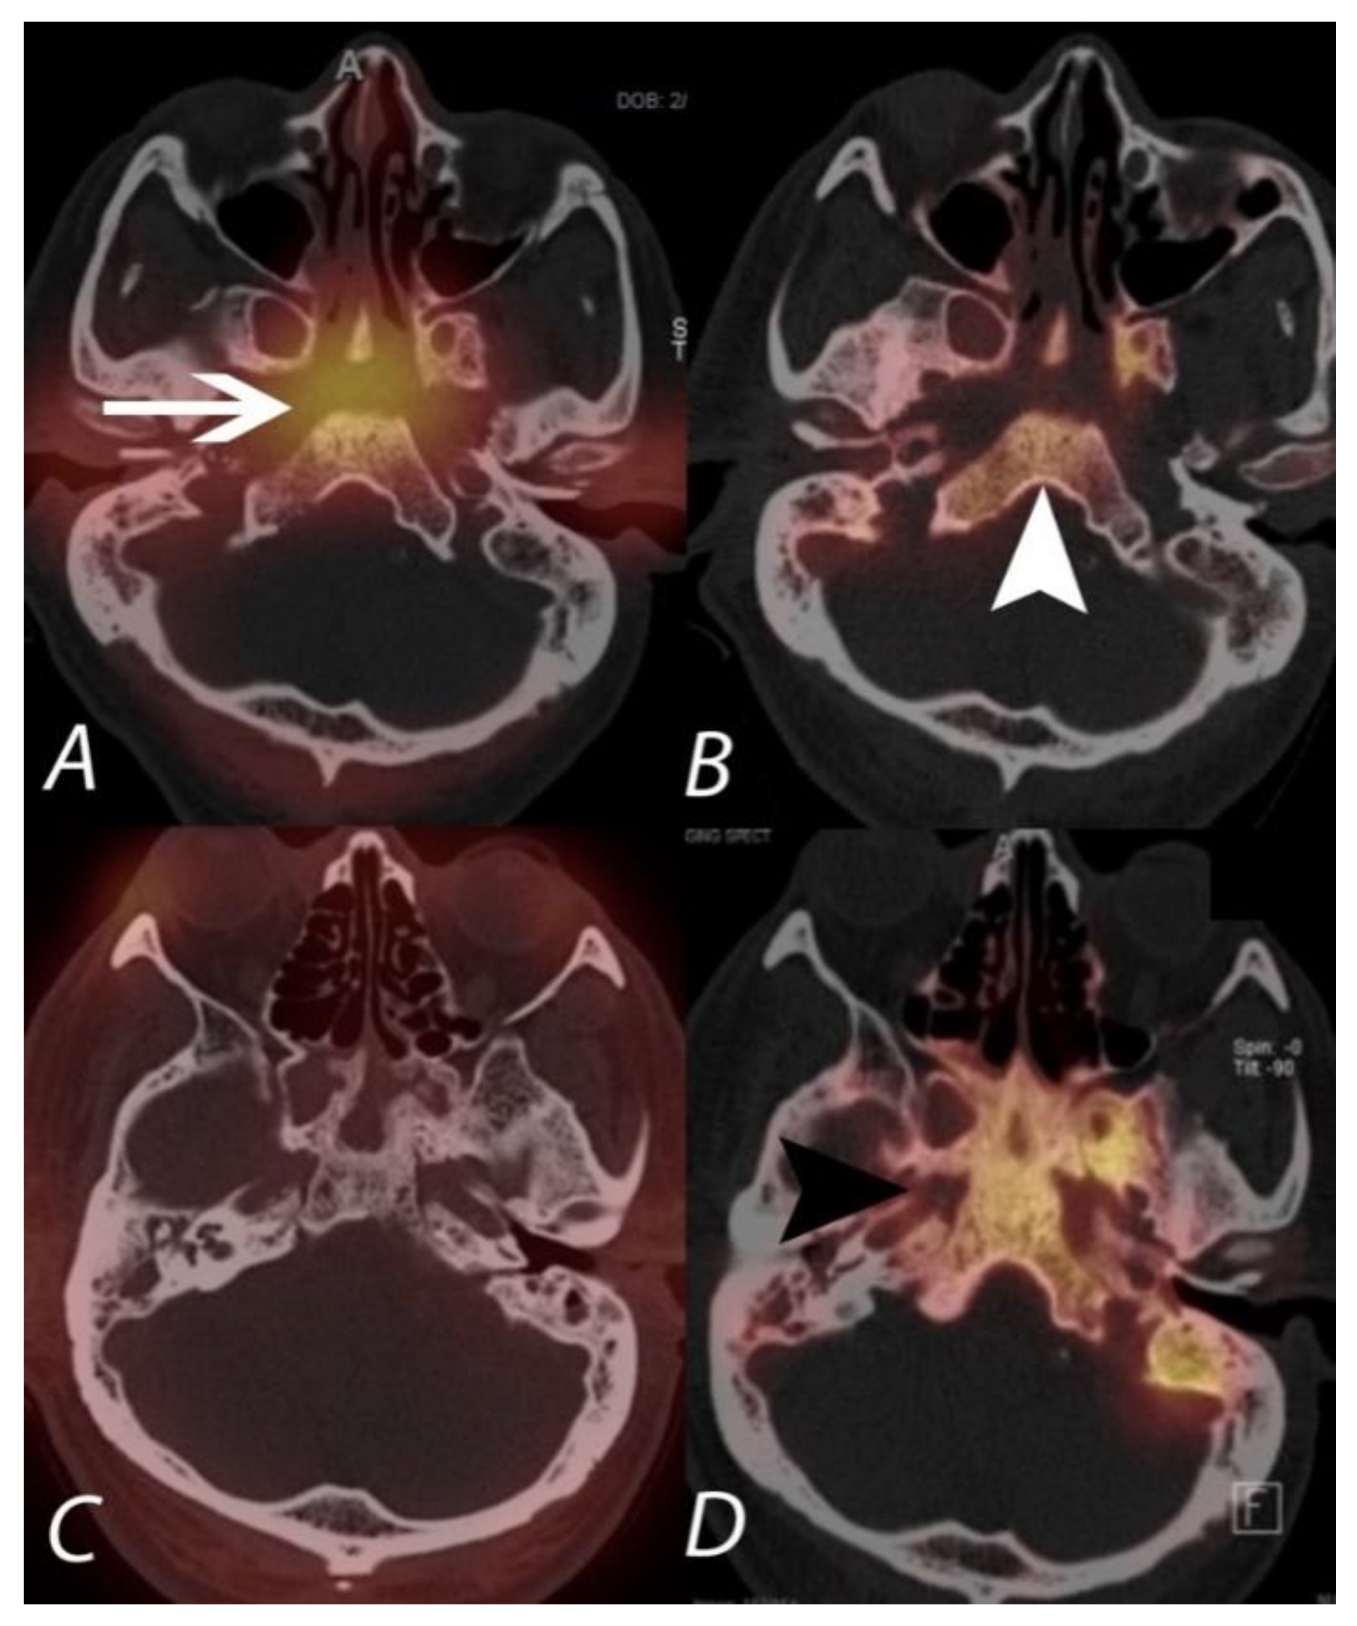

Figure 15.

The upper panel (A,B) demonstrates 67Ga and 99mTc MDP SPECT/CT scans in a patient being evaluated for acute malignant otitis externa. While 99mTc MPD SPECT/CT shows uptake in the bones of the central skull base (white arrowhead), consistent with osteomyelitis, the 67Ga also demonstrates soft tissue infection at the central skull base and around the external auditory canals. The lower panel (C,D) is of a different patient with continued pain following completion of an antibiotic regimen for skull base osteomyelitis. The 99mTc MDP SPECT/CT (right lower panel) shows post-infectious remodeling hyperostosis of the bones of the central skull base, but the 67Ga SPECT/CT (left lower panel) shows an absence of active infection.